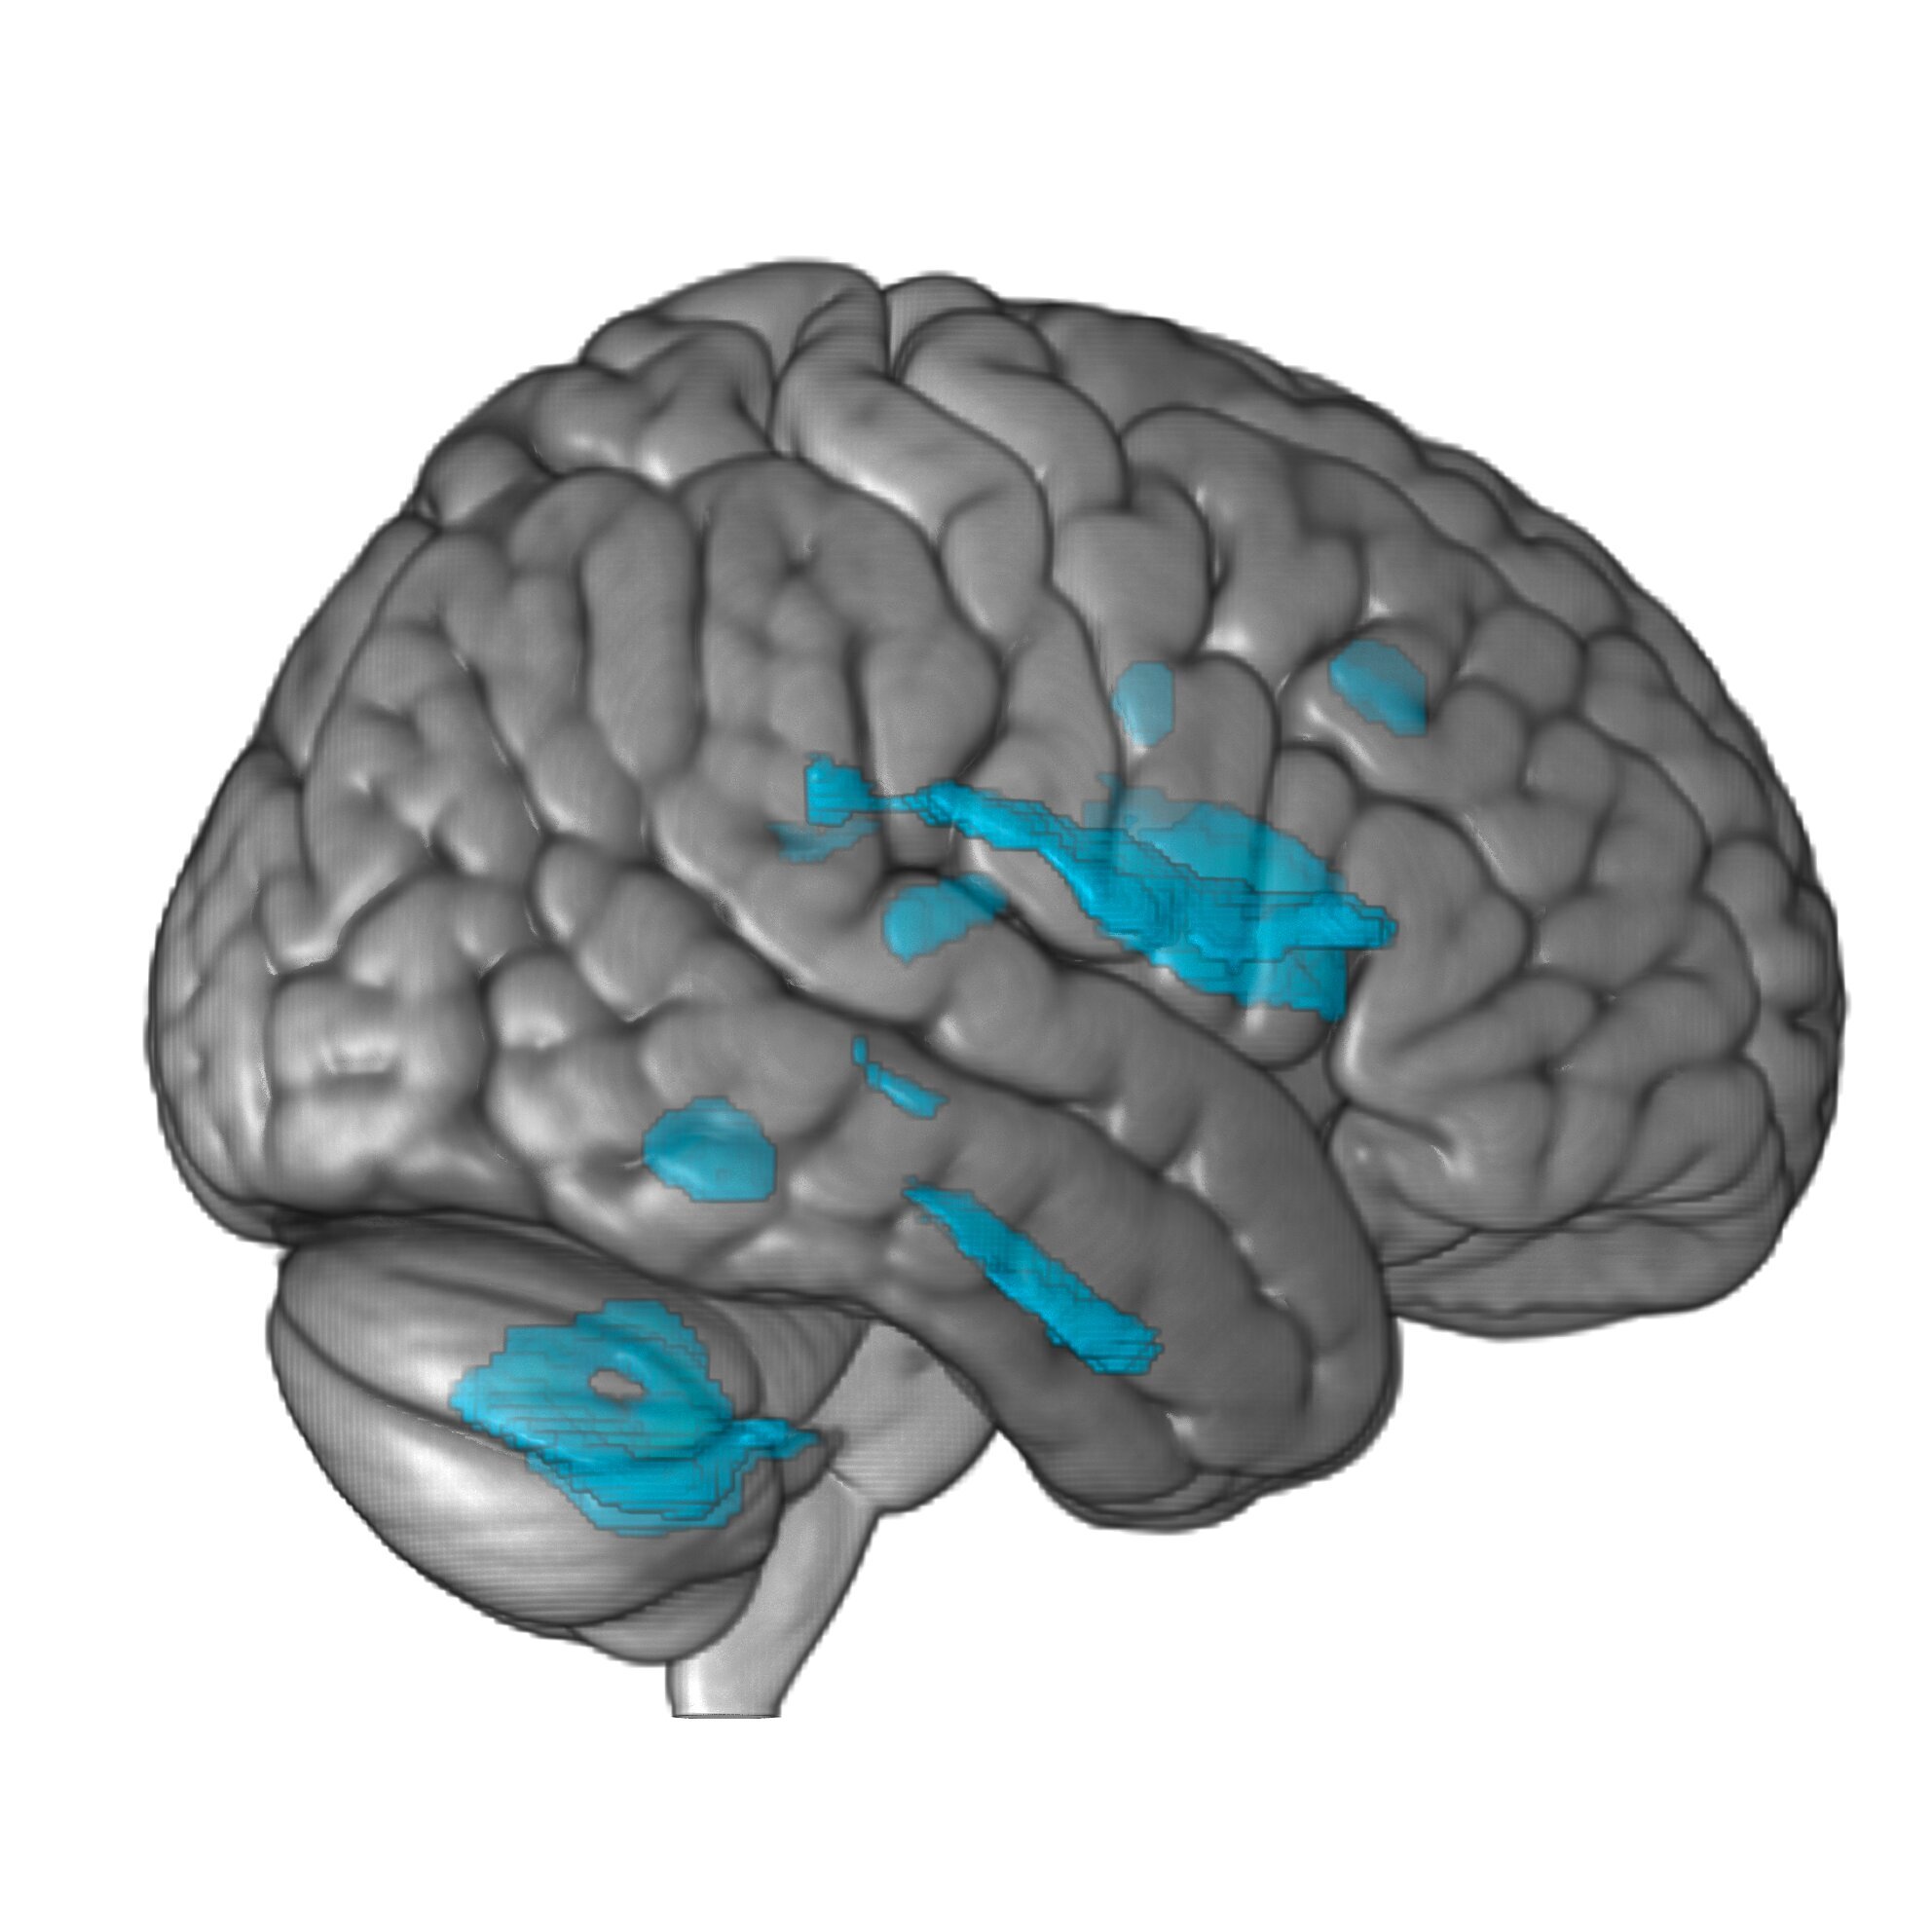

Спустя полгода оказалось, что у людей увеличилось количество серого вещества в четырёх областях мозга, которые участвуют в когнитивных функциях высокого уровня. Так, производительность мозжечка увеличилась на 6%.

Кроме того, у пианистов объём серого вещества оставался стабильным в правой первичной слуховой коре – ключевой области обработки звука, а у тех, кто занимался активным слушанием, объём этого вещества уменьшался. Также у всех участников наблюдалась атрофия мозга. То есть занятия музыкой всё-таки предотвращают старение мозга в определённых его областях.